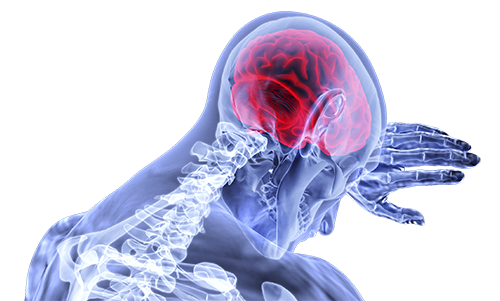

Cubre daños corporales que puedas sufrir como consecuencia de un accidente, ya sea en tu trabajo o en tu vida cotidiana.

Cubre daños corporales que puedas sufrir como consecuencia de un accidente, ya sea en tu trabajo o en tu vida cotidiana.

Cubre daños corporales que puedas sufrir como consecuencia de un accidente, ya sea en tu trabajo o en tu vida cotidiana.

Cubre daños corporales que puedas sufrir como consecuencia de un accidente, ya sea en tu trabajo o en tu vida cotidiana.